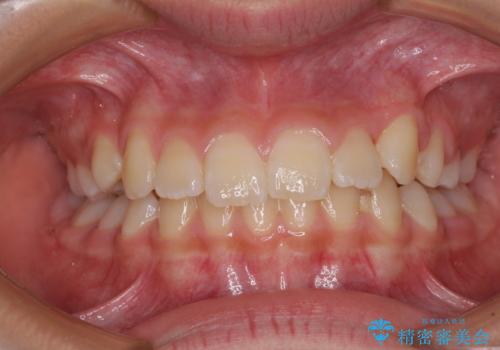

今後残っている乳歯が抜け、永久歯が萌出してくるため、調整可能なリンガルアーチを用いて保定を行っています。

12歳臼歯が萌出するまで経過観察を行い、すべての歯が萌出した後に、全顎矯正治療(Ⅱ期治療)を行っていきます。